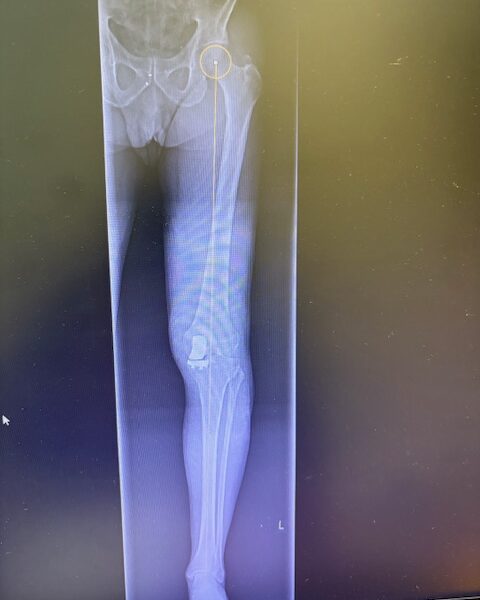

Ο ακτινολογικός έλεγχος (ακτινογραφίες/μαγνητική τομογραφία) ανέδειξε προχωρημένη οστεοαρθρίτιδα του έσω κονδύλου, με πλήρη διατήρηση του έξω διαμερίσματος και της επιγονατιδομηριαίας άρθρωσης. Με βάση αυτά τα ευρήματα, ο ασθενής ήταν ιδανικός υποψήφιος για μερική (μονοκονδυλική) αρθροπλαστική γόνατος.

Πραγματοποιήθηκε απεικόνιση και ψηφιακός σχεδιασμός της επέμβασης, ώστε να προσδιοριστεί με ακρίβεια το μέγεθος και η θέση των προθέσεων. Ο στόχος ήταν να αποκατασταθεί η φυσιολογική μηχανική του γόνατος, διατηρώντας ανέπαφα τα υγιή τμήματα της άρθρωσης, τους συνδέσμους και τους γύρω μυς.